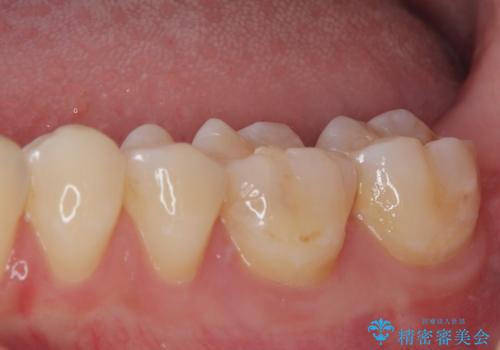

- 奥歯が食事の度にしみてしまうとのことで来院された患者様です。

目視やレントゲン写真からは、以前処置された部分に大きな問題は認められませんでしたが、冷たい風をかけると強い痛みを感じる状態でした。

患者様と相談の上、詰め物を全て外した上でむし歯があるかどうかを確認し、セラミックインレーで精密な修復治療を行うこととしました。